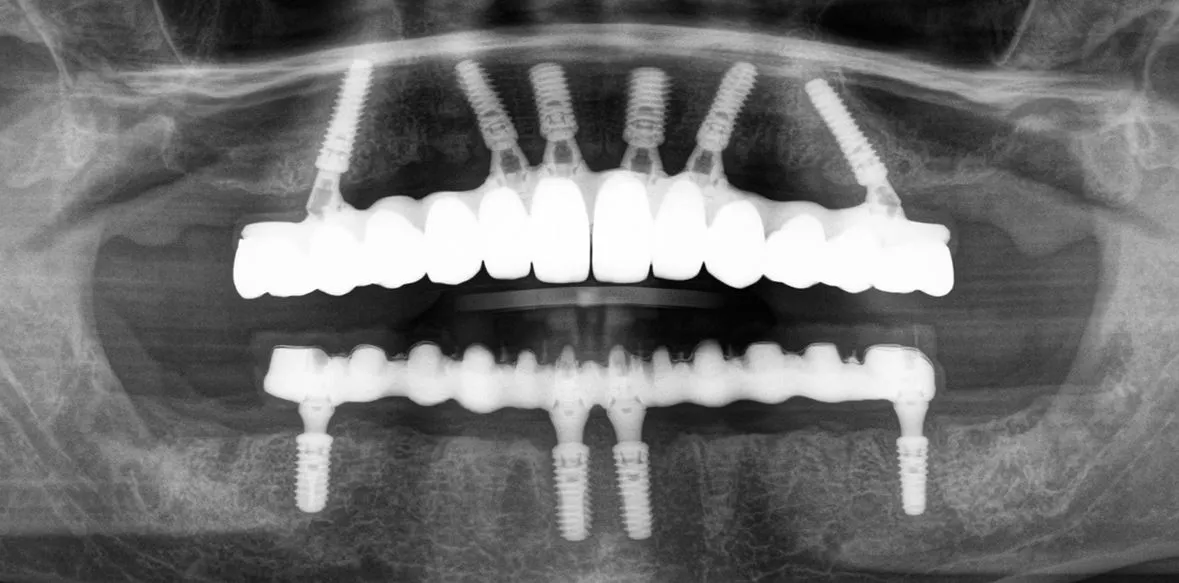

Daher haben sich in der Vergangenheit zum Beispiel Zentren für die Durchführung der Implantatplanung etabliert [6]. Für die prothetisch orientierte Planung benötigt das Planungszentrum neben den Informationen über die gewünschte Position und Anzahl der Implantate und die Unterlagen über das Knochenangebot, die anatomische Struktur und die Bißlage. Diese Daten können über konventionelle Abdrücke oder intraorale Scans der Kiefer, sowie mittels dreidimensionaler Röntgenaufnahmen zur Verfügung gestellt werden (Abb. 1-3). Mit diesen Unterlagen kann dann die Implantatplanung mit Umsetzung einer Navigationsschablone sowie die Herstellung eines Provisoriums erfolgen [4].

Zur genauen Abstimmung kann die Planung über einen Online-Zugriff auf den Planungscomputer mittels eines Screen-Sharingsprogramms zwischen Behandler und Zahntechniker diskutiert werden. Sofern die Planung den Erwartungen des chirurgisch tätigen Zahnarztes entspricht, kann der Vorschlag angenommen und für die Produktion freigegeben werden (Abb. 8). Die Produktion der Bohrschablone und des Provisoriums erfolgt dann im Fertigungszentrum. Nach Fertigstellung werden alle benötigen Systemkomponenten mit den zahntechnischen Werkstücken versandt.

im Oberkiefer bei dünner Kortikalis oftmals durch ein festeres Einpressen positioniert werden. Im Unterkiefer wird über die Hülse für den Fixationspin in der Regel eine Vorbohrung notwendig. Nach der genauen Lagesicherung der Navigationsschablone kann dann die komplette Bohrerabfolge geführt bis zur Implantatinsertion angewendet werden. Im Anschluss werden die bei der Planung definierten geraden und angulierten Abutments eingesetzt und die Titanzylinder für das Einkleben des Provisoriums fixiert [1]. Nach dem Einkleben der Zylinder in das Provisorium muss diese nochmals ausgearbeitet werden und die Sofortversorgung ist abgeschlossen (Abb. 11-12).

In einem nächsten Schritt kann man dann eine geführte Einzelzahnsofortversorgung durchführen. Der gezeigte Fall stellt den Abschluss einer solchen Entwicklung dar. Die Plattform erleichtert dem Anwender auch komplexe Versorgungen mit vertretbarem Aufwand sicher und mit einem geringen Komplikationsrisiko zu erreichen (Abb. 13-14). Nach einer Einarbeitung mit dem digitalen Workflow, können dann wieder je nach Investitionsvolumen Arbeitsschritte in der eigenen Praxisstruktur etabliert werden, um den Leistungsumfang wieder stärker in der praxiseigenen Prozesskette einzubinden.